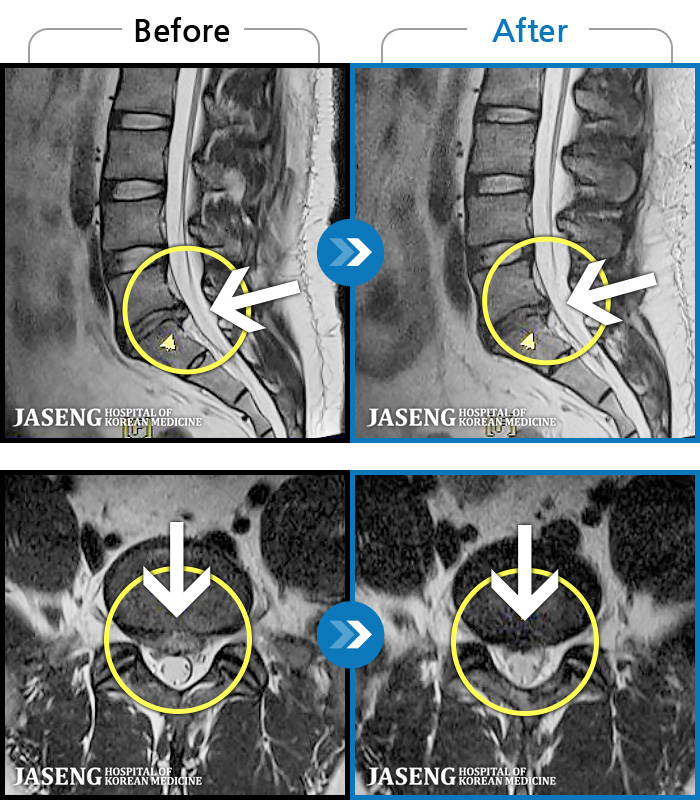

[뱸] 19.11.28~25.05.06